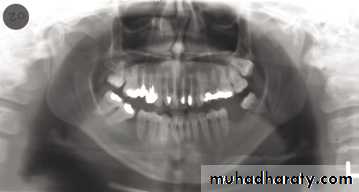

1, Mandibular condyle. 2, Articular eminence. 3, Coronoid process of mandible superimposed on zygomatic arch. 4, Posterior wall of maxillary sinus. 5, Posterior wall of zygomatic process of maxilla. 6, Hard palate. 7, Nasal septum. 8, Tip of nose. 9, Dorsum of tongue. 10, Hyoid superimposed over inferior border of mandible. 11, Inferior border of maxillary sinus. 12, Image of cervical spine. 13, Medial border of maxillary sinus. 14, Infraorbital canal. 15, Infraorbital rim. 16, Pterygomaxillary fissure. 17, Anterior border of the pterygoid plates. 18, Lateral pterygoid plate superimposed over soft palate and coronoid process of mandible. 19, Ear lobe. 20, Inferior border of mandibular canal. 21, Mental foramen. 22, Posterior wall of nasopharynx. 23, Inferior border of mandible superimposed from opposite side. 24, Soft palate over mandibular foramen of mandible.